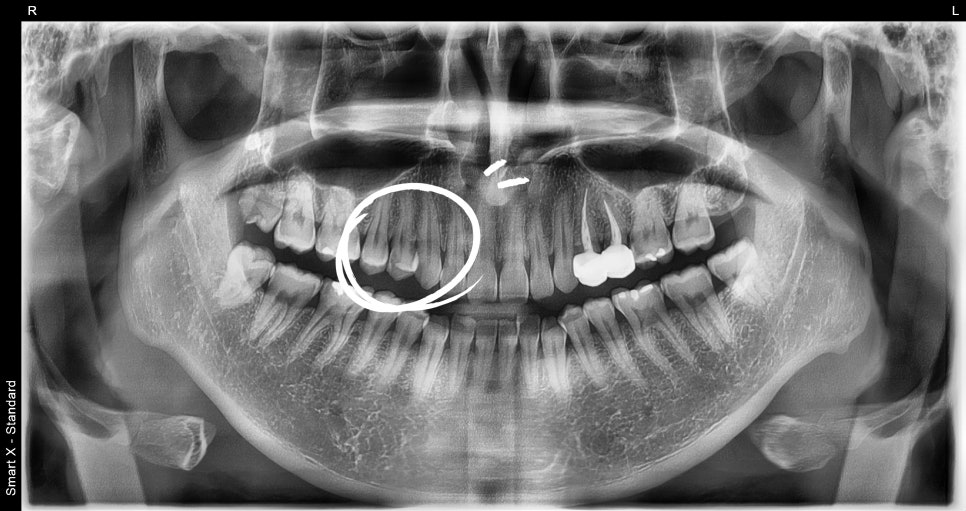

After checking the photos and X-rays taken at the dental clinic,

bacteria had entered through the crack,

and the nerve was already severely damaged.

If left like this, the pain would gradually worsen,

and eventually it could lead to a situation where extraction and an implant are needed,

so we explained that root canal treatment was needed right away.